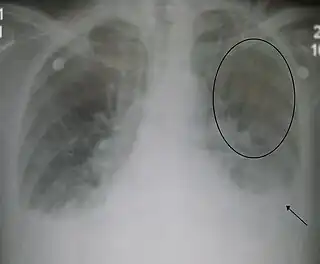

La radiografía de tórax con frecuencia puede asistir en el diagnóstico de una IC. En el paciente compensado, puede mostrar cardiomegalia (agrandamiento visible del corazón), cuantificada como la proporción del tamaño del corazón en el pecho. En la insuficiencia cardíaca izquierda puede haber evidencia de redistribución vascular, líneas de Kerley, pérdida de definición bronquial y edema intersticial.[18]